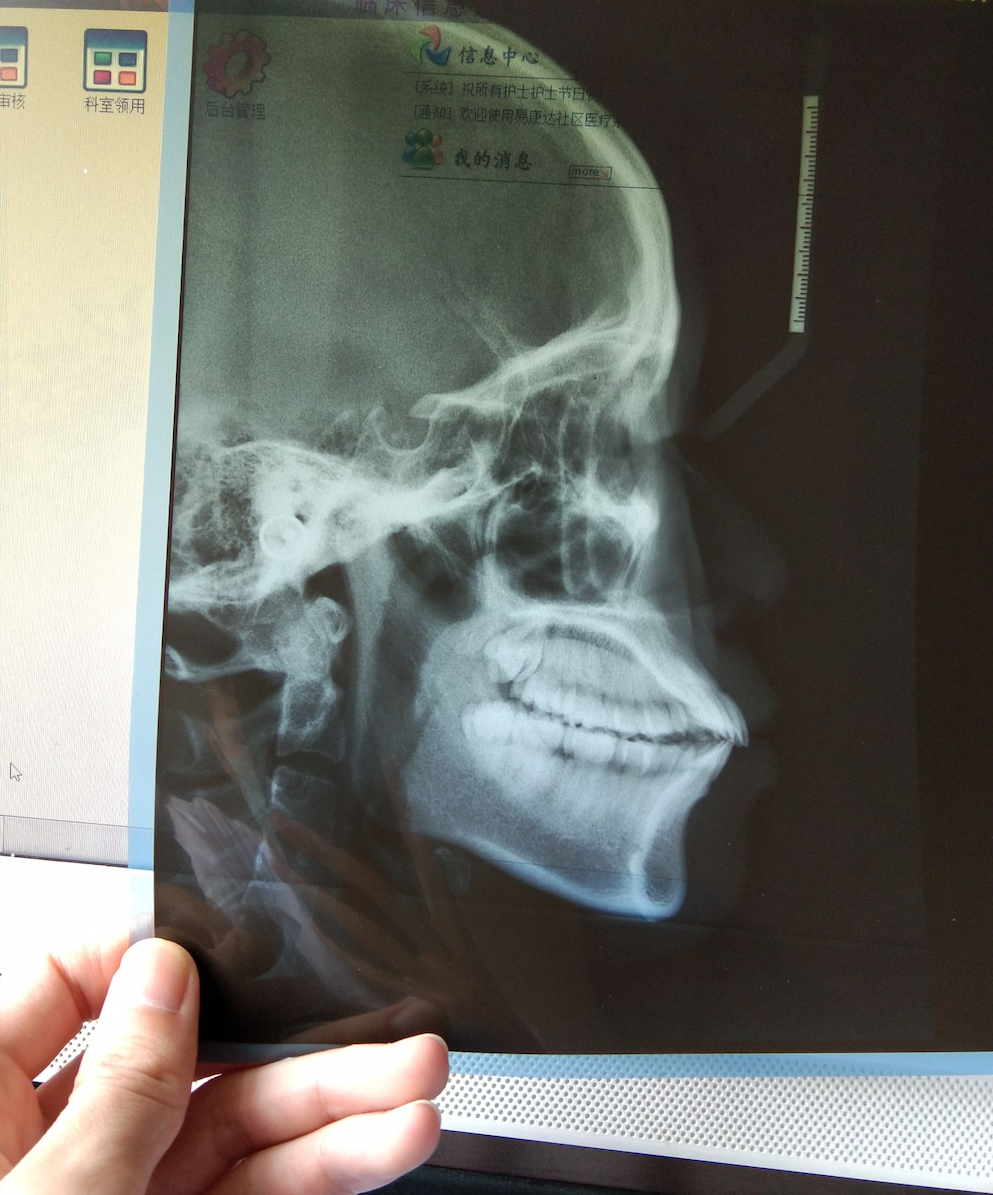

演示图片4

精确识别头颅侧位片中17个关键解剖标志点